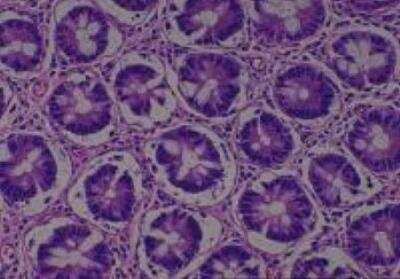

Hematoxylin & Eosin Stain: Human Common Tissue MicroArray (Normal Adjacent) [NBP2-30215] - 01. Stomach